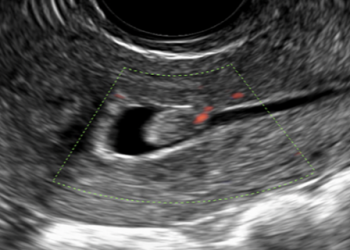

Cari soci, questo mese un nuovo video "How to do", sulla modalità di acquisizione dei volumi 3D e 4D in...